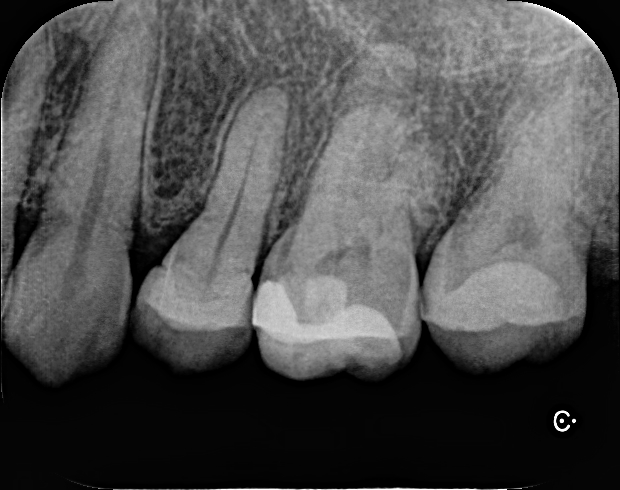

歯の状態を見させていただきました。現状から、痛みが続いているのは3つの理由があると考えられます。1つめは、虫歯がまだ残っている状態が原因と思われます。痛みを取り除くには、根の中の細菌をしっかりと減らす必要があります。しかし、虫歯がある状態では根の中に持続的な感染が続くため、痛みが続く原因となります。

この写真を見てびっくりしました。てっきり虫歯は全部取り切っているいるものと思っていました…